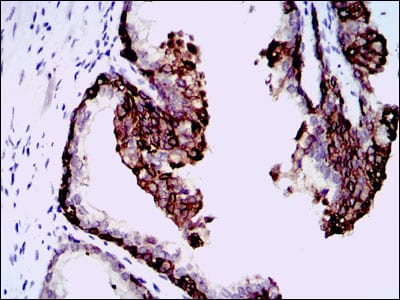

分类: 科研抗体货号: 30353别名: CEBP; C/EBP-alpha应用: WB,IHC,IF,FCM反应种属: Human